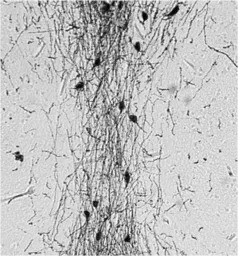

IHC-P analysis of Hyla cinerea (green treefrog) forebrain tissue using GTX79310 GnRH antibody.

Dilution : 1:1000

IHC-P analysis of mouse embryo brain tissue using GTX79310 GnRH antibody.